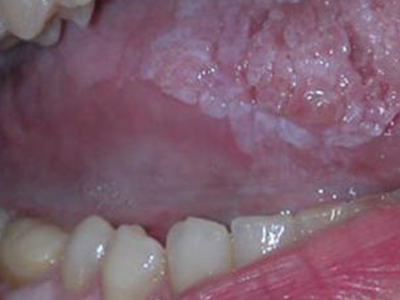

口癣一般指口腔扁平苔藓,是累及口腔,与细胞介导免疫功能紊乱有关的慢性炎症性疾病。好发于中年人,且女性多于男性,通常病程较长。患病后,临床特征为口腔黏膜损害,早期没有自觉症状,也容易被忽视,多在检查时偶然发现,其具体病因不明,通常在治疗时也需给予药物治疗及生活调理。

口癣的临床特征为口腔黏膜损害,主要为珠光白色条纹或网纹,也可为单线条或绕成环形。在舌背多为圆形或椭圆形白色斑块,损害区乳头消失而平伏。软腭或其他部位可发生透明颗粒状水疱。条纹之间的黏膜色泽可以正常或充血;有时在损害范围内某一区域发生糜烂,在唇部或颊黏膜处有时可出现针头大小、微隆的丘疹。